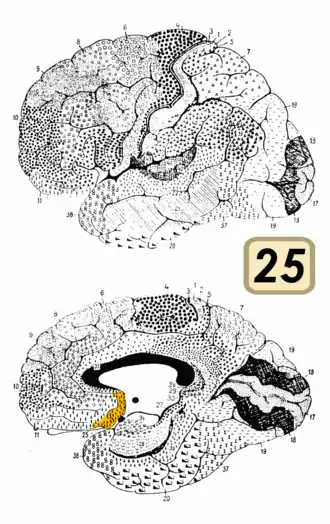

Brodmann area 25

Brodmann area 25 is shown in orange. | |

Brodmann area 25 (BA25) is the subgenual area, area subgenualis or subgenual cingulate area in the cerebral cortex of the brain and delineated based on its cytoarchitectonic characteristics.

It is the 25th "Brodmann area" defined by Korbinian Brodmann. BA25 is located in the cingulate region as a narrow band in the caudal portion of the subcallosal area adjacent to the paraterminal gyrus. The posterior parolfactory sulcus separates the paraterminal gyrus from BA25. Rostrally it is bound by the prefrontal area 11 of Brodmann.[1]